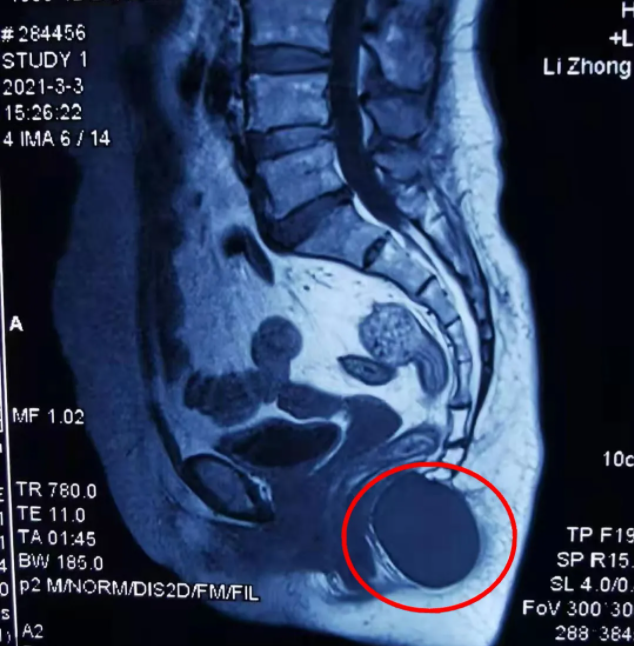

曾女士在家人的陪伴下辗转多家医院,均考虑是混合痔,但吃了一段时间治疗痔疮的药后也未见好转,直到在市内一家医院做了核磁共振检查,看结果才发现曾女士的尾椎下方有一个4cm*4cm如鸡蛋大小的肿块,已经压迫到直肠和骶尾神经,必须马上进行手术切除。但由于肿块太大,周围的神经、血管丰富,手术难度相当大,辗转几家医院都不敢为她动手术,此时曾女士更急了……

曾女士的亲戚得知这个情况,抱着试一试的态度带她来到我院外科求医,入院后,曾女士进一步完善相关检查,初步诊断为“骶尾部后腹膜表皮样囊肿”,且肿块边界清楚,未侵犯周围软组织,良性肿瘤可能性大,肿块已由骶尾部延伸,通过尾骨尖端,进入盆腔,位置深,位于腹膜后直肠前,要完整切除肿块,术中很有可能损伤盆底重要血管,输尿管,盆腔及骶尾部神经等,病情比较复杂,手术切除非常困难。